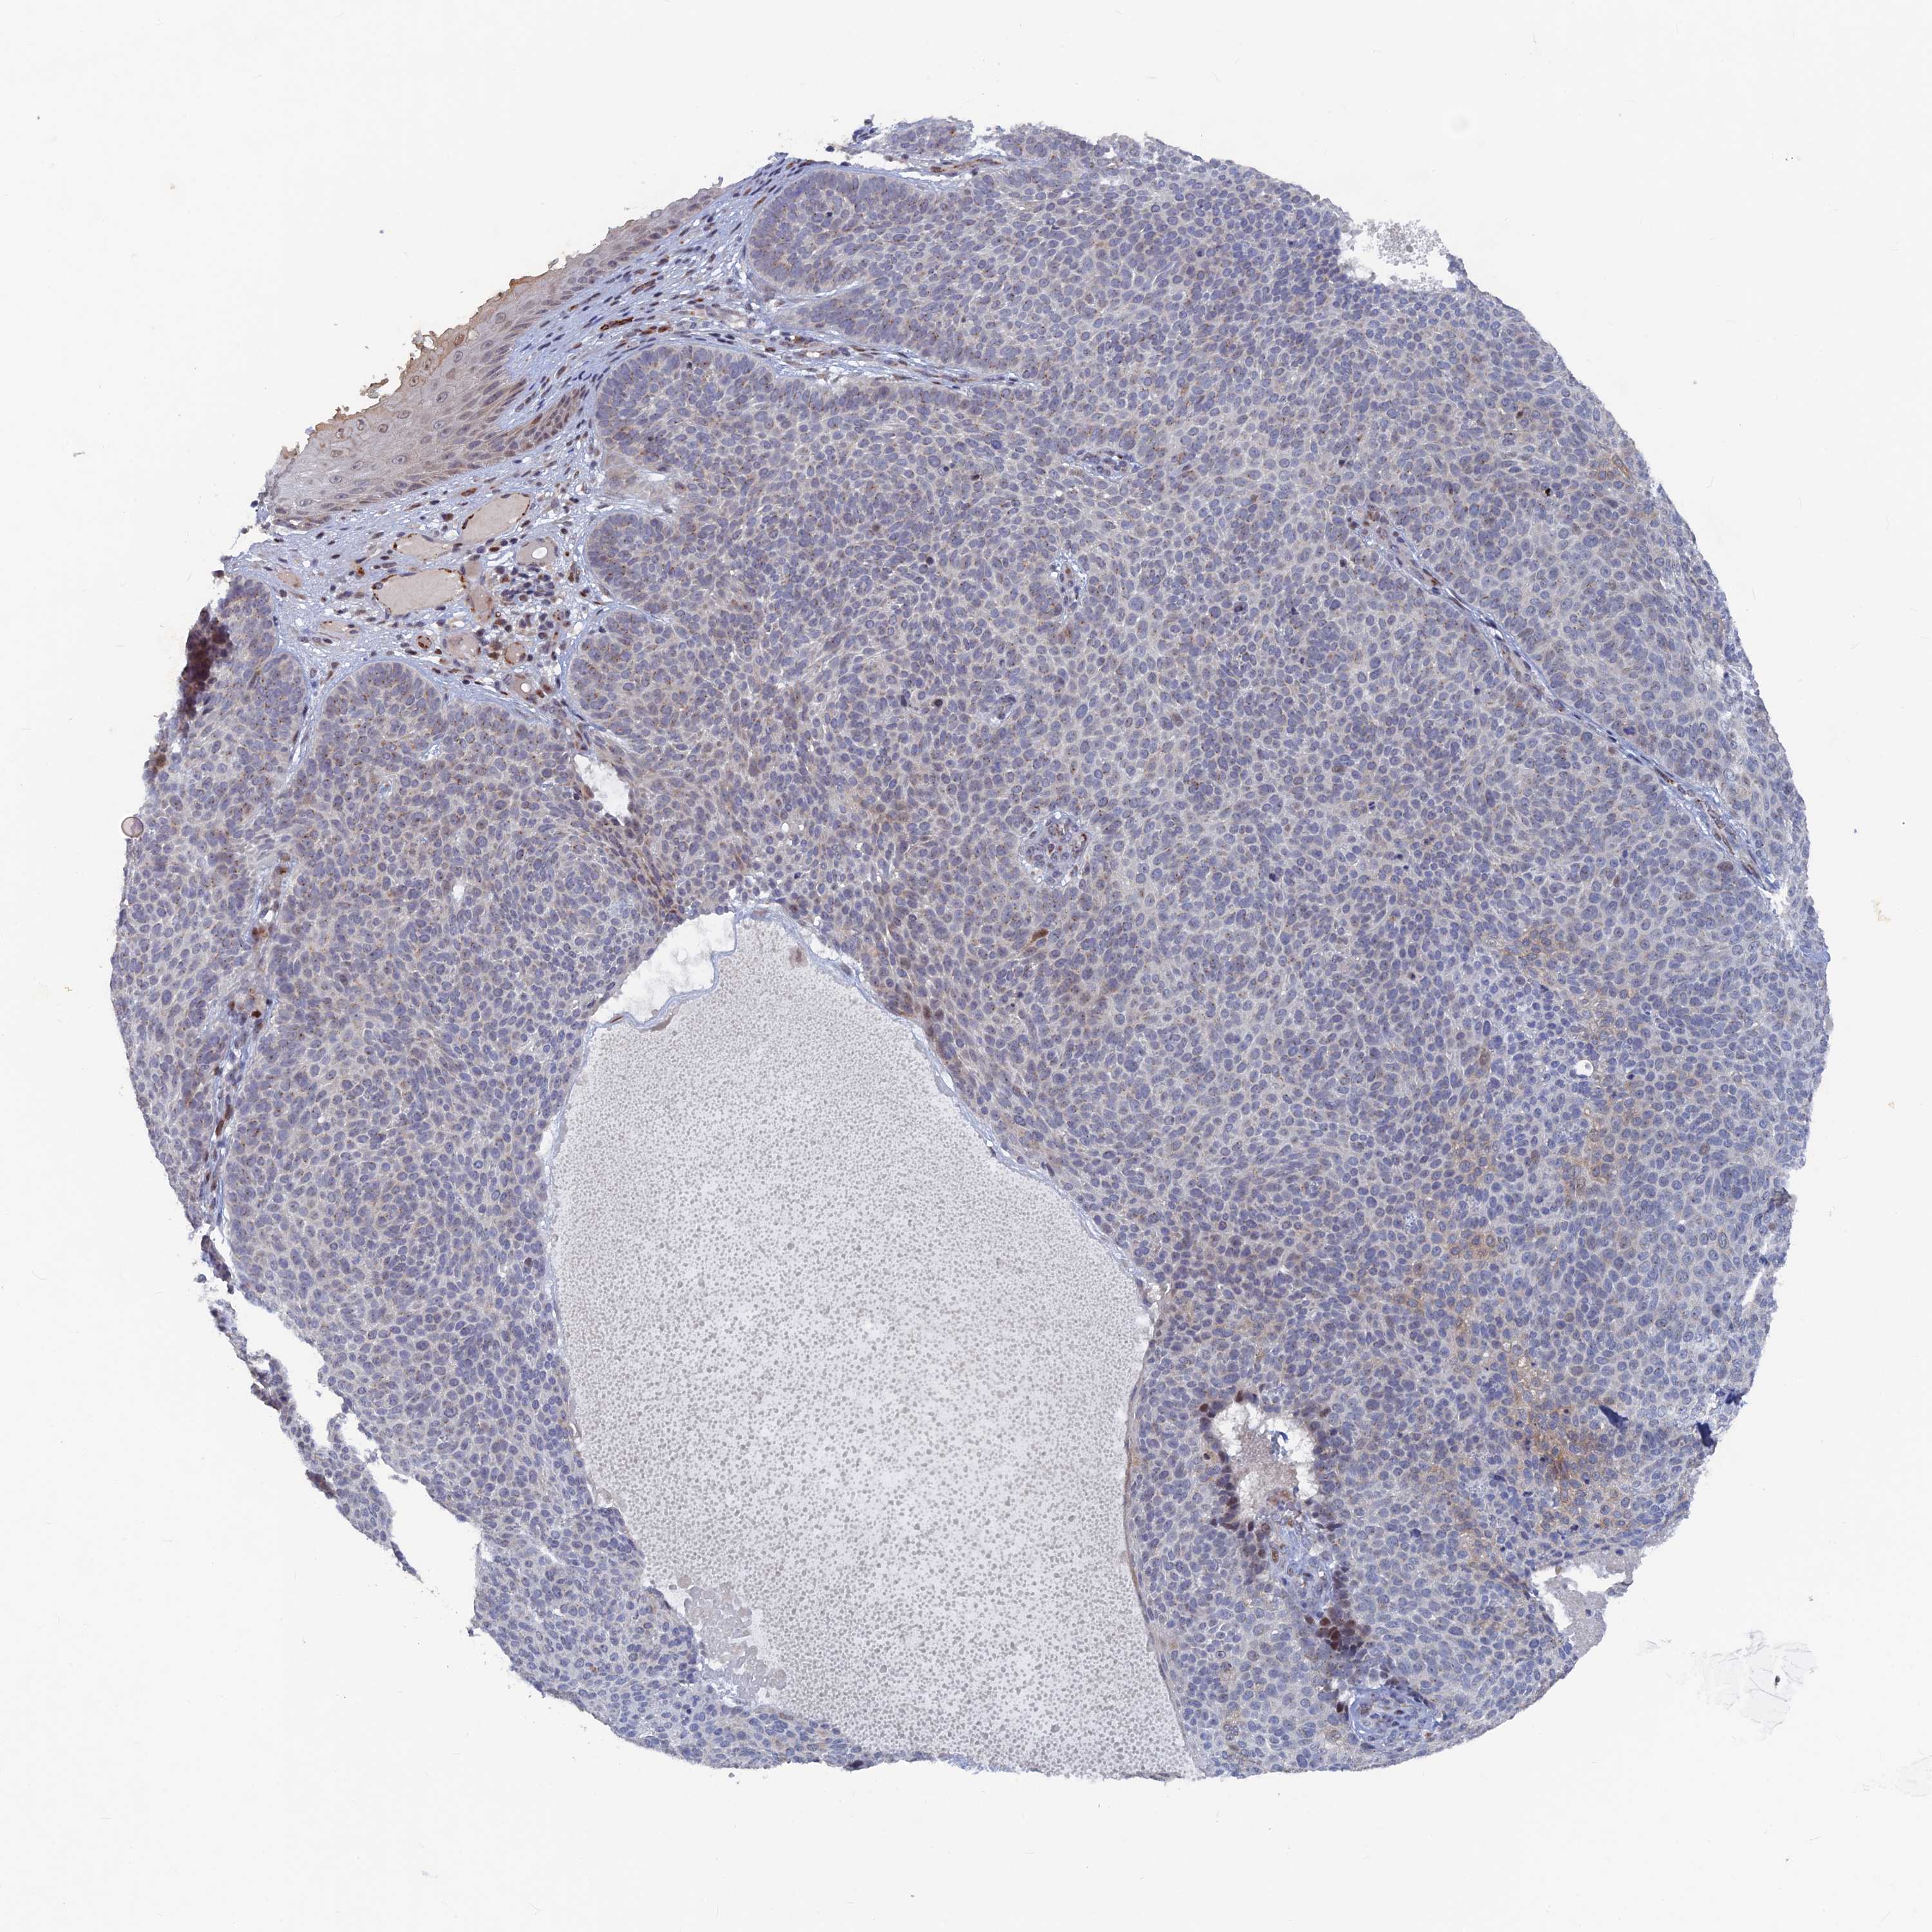

Basal cell and squamous cell cancer

SKIN CANCER - Protein expressioni

A mouse-over function shows sample information and annotation data. Click on an image to view it in a full screen mode. Samples can be filtered based on level of antibody staining by selecting one or several of the following categories: high, medium, low and not detected. The assay and annotation is described here.

Each image is clickable and will lead to virtual microscopy that enables deeper exploration of all samples and also displays staining intensity scores, fraction scores and subcellular localization as well as patient and tissue information for each sample.

Antibody HPA042212

Antibody HPA042456

Squamous cell carcinoma, NOS